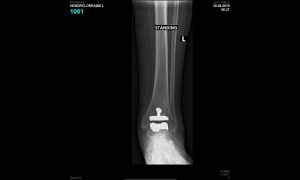

This is a graphic illustration of the Salto ankle prosthesis on the left and XR of the prosthesis in the ankle following the surgery for a patient with traumatic arthritis.